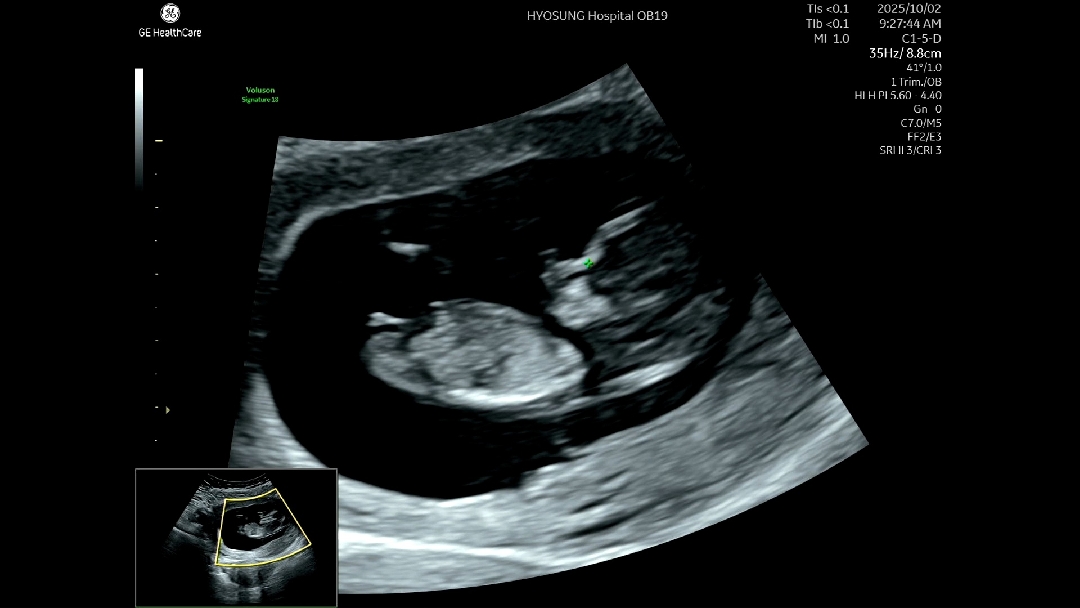

각도법 봐주새요

각도법 봐주세요